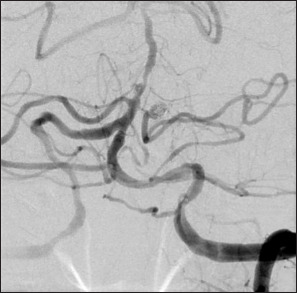

Case description: A 77-year-old woman presented with a sudden headache and computed tomography showed a subarachnoid hemorrhage predominant in the left cerebellopontine angle. Cerebral angiography revealed a saccular aneurysm in the anterior pontine segment of the left AICA. Coil embolization underwent preserving the parent artery. There is no recanalization of the aneurysm at 26 months postoperatively. In this case, hemodynamic stress was suggested to be involved in the development of the aneurysm.